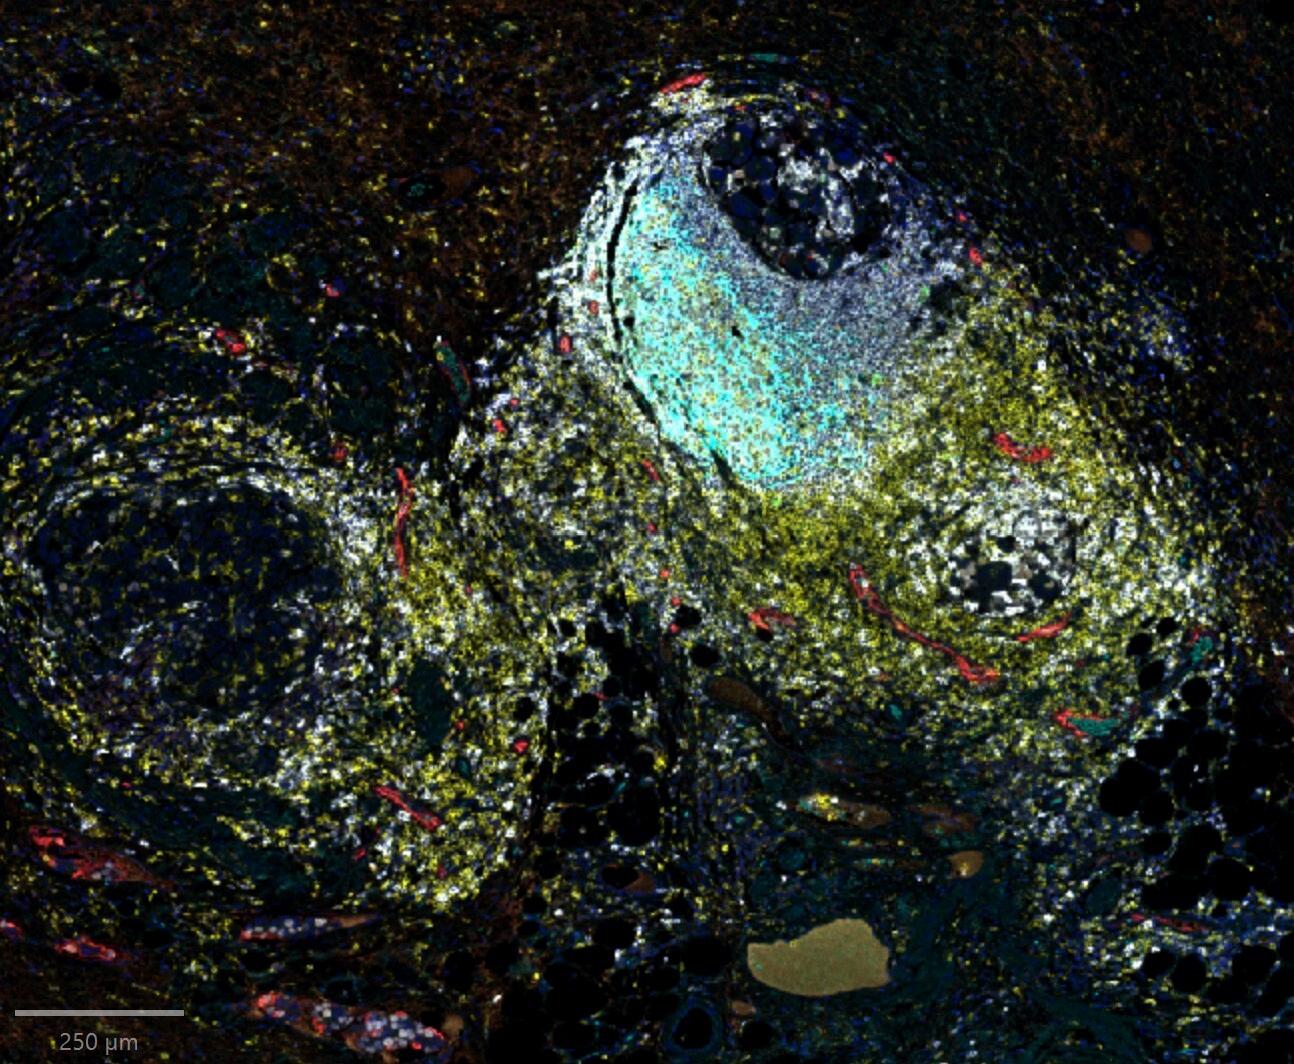

Dr. Buckanovich’s laboratory studies a population of inherently therapy resistant ‘quiescent’ cancer cells which are a primary driver of disease recurrence and death. These quiescent cells can not only increase chemotherapy resistance in neighboring cancer cells but also inactivate anti-tumor immune responses with the combined effect to drive cancer recurrence and growth. His lab is developing new therapies to selectively target these quiescent cells to prevent ovarian cancer deaths helping mothers live longer to care for their families.

Quiescent cell targeted therapies to prevent chemotherapy resistance and recurrence

Humanized immune and stroma tumor model for preclinical drug testing

The Cascio Lab focuses on elucidating signaling interactions in the ovarian tumor microenvironment, particularly how stromal and tumor-secreted factors reprogram myeloid cell function Combining murine models with patient-derived samples, we aim to identify targets like EGFL6, TGFBI, and Periostin to boost immunotherapy efficacy We offer collaboration potential in developing precision immunotherapies targeting the tumor microenvironment including biologics against EGFL6, myeloid cell reprogramming agents, and combination strategies to overcome checkpoint blockade resistance Preclinical validation and biomarker development are ongoing